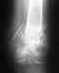

В августе 2009 была сделана операция (трех лодыжечный перелом. После снятия швов на внутренней стороне ноги образовался некроз.

Сейчас стала отваливаться болячка и внутри дырки показался болт, кожи на нем нет и начало гноиться. Была в пятницу в больнице они болт не увидели, а сегодня гной убрала и стала видна шляпка болта. Подскажите ,что делают в подобной ситуации? Спасибо.